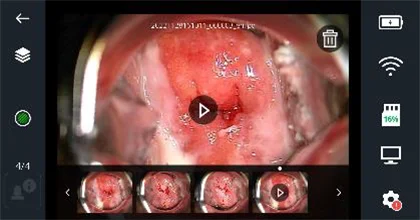

Дүрс бичлэгийн хувьд тоглуулах товчлуур дэлгэцний голд гарч ирнэ, Зураг 14 (a)-г үзнэ үү! Тоглуулах товчийг дарсны дараа видео тоглуулах болно, Зураг 14 (b).

Зураг 14 (a) - Дүрс бичлэг тоглуулах товчлуур бүхий дэлгэцний харагдац